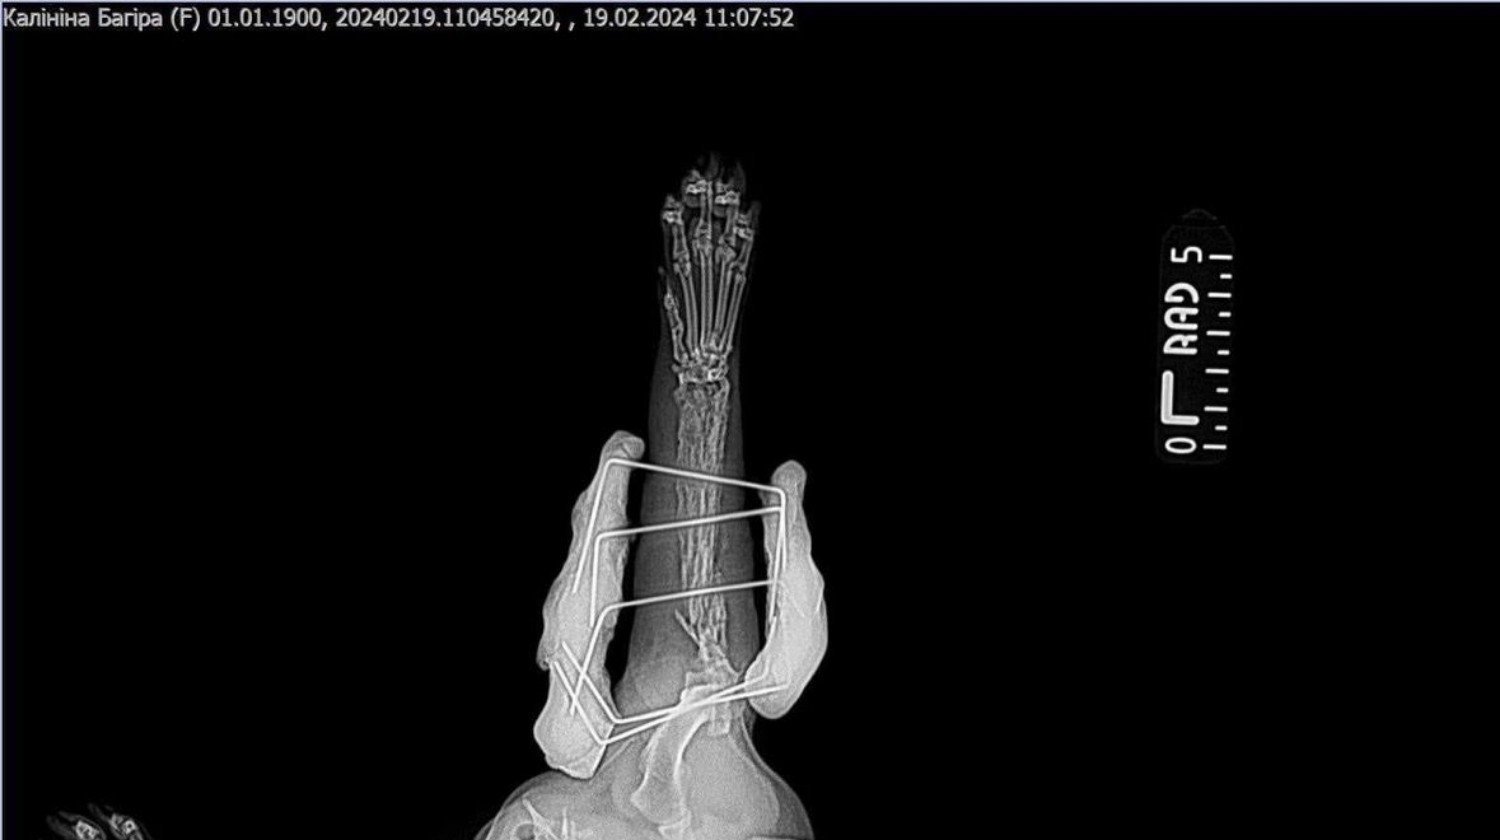

Bo Lesia przeszła złamanie i obecnie jej łapka nadaje się do amputacji, co na Ukrainie było niemożliwe do wykonania. Lesia przyjechała więc do nas spod Kijowa transportem, na który czekała wiele tygodni. Baliśmy się już, że wszystko się nie uda, bo nikt nie chciał ryzykować dla bezpańskiego, czarnego kota. Ale w ostatniej chwili okazało się, że jednak ktoś jedzie w tym kierunku i Lesię udało się przetransportować. Jak wiecie, tamte zwierzęta nie mają szczęścia. Do niczego. Chociaż nie są winne tej całej wojny, to jednak płacą za nią ogromną cenę.